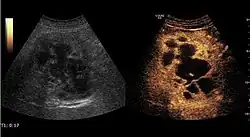

HCC appearance on 2D ultrasound is that of a solid tumor, with imprecise delineation, with heterogeneous structure, uni- or multilocular (encephaloid form). An "infiltrative" type is also described which is difficult to discriminate from liver nodular reconstruction in cirrhosis. Typically HCC invades liver vessels, primarily the portal veins but also the hepatic veins . Doppler examination detects a high speed arterial flow and low impedance index (correlated with described changes in tumor angiogenesis). The spatial distribution of the vessels is irregular, disordered. CEUS examination shows hyperenhancement of the lesion during the arterial phase. During the portal venous phase there is a specific "wash out" of ultrasound contrast agent (UCA) and the tumor appears hypoechoic during the late phase. Poorly differentiated tumors may have a stronger wash out leading to an isoechoic appearance to the liver parenchyma during portal venous phase. This appearance was found in approx. 30% of cases. The described changes have diagnostic value in liver nodules larger than 2 cm.